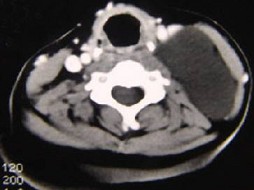

5.男性,40岁,颈部出现无痛性囊性包块2年余,CT扫描如图所示,最可能诊断为  (    )

正确答案:A